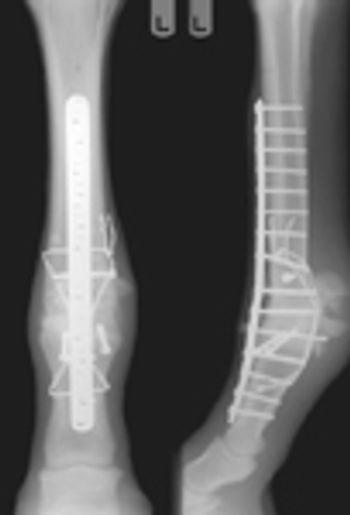

Types of musculoskeletal trauma: wounds and lacerations, skin, deep structures (tendon, ligament, joint, bone), vascular injury, nerve injury, fracture.